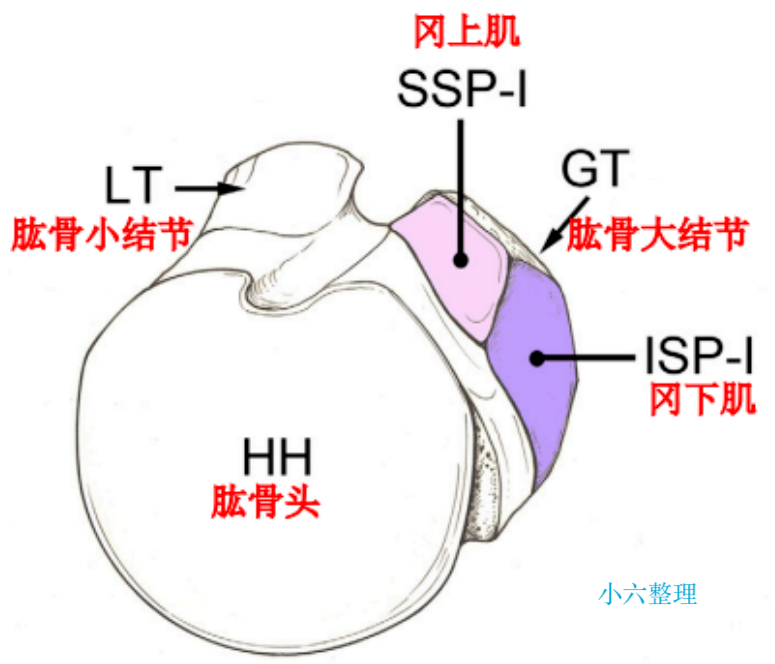

Park 等认为对于运动员或需要手臂过头的体力劳动者,大结节骨块发生 0.3 cm 的移位也应当手术复位;

单纯大结节骨折移位较大甚至突入肱骨头及肩峰之间。